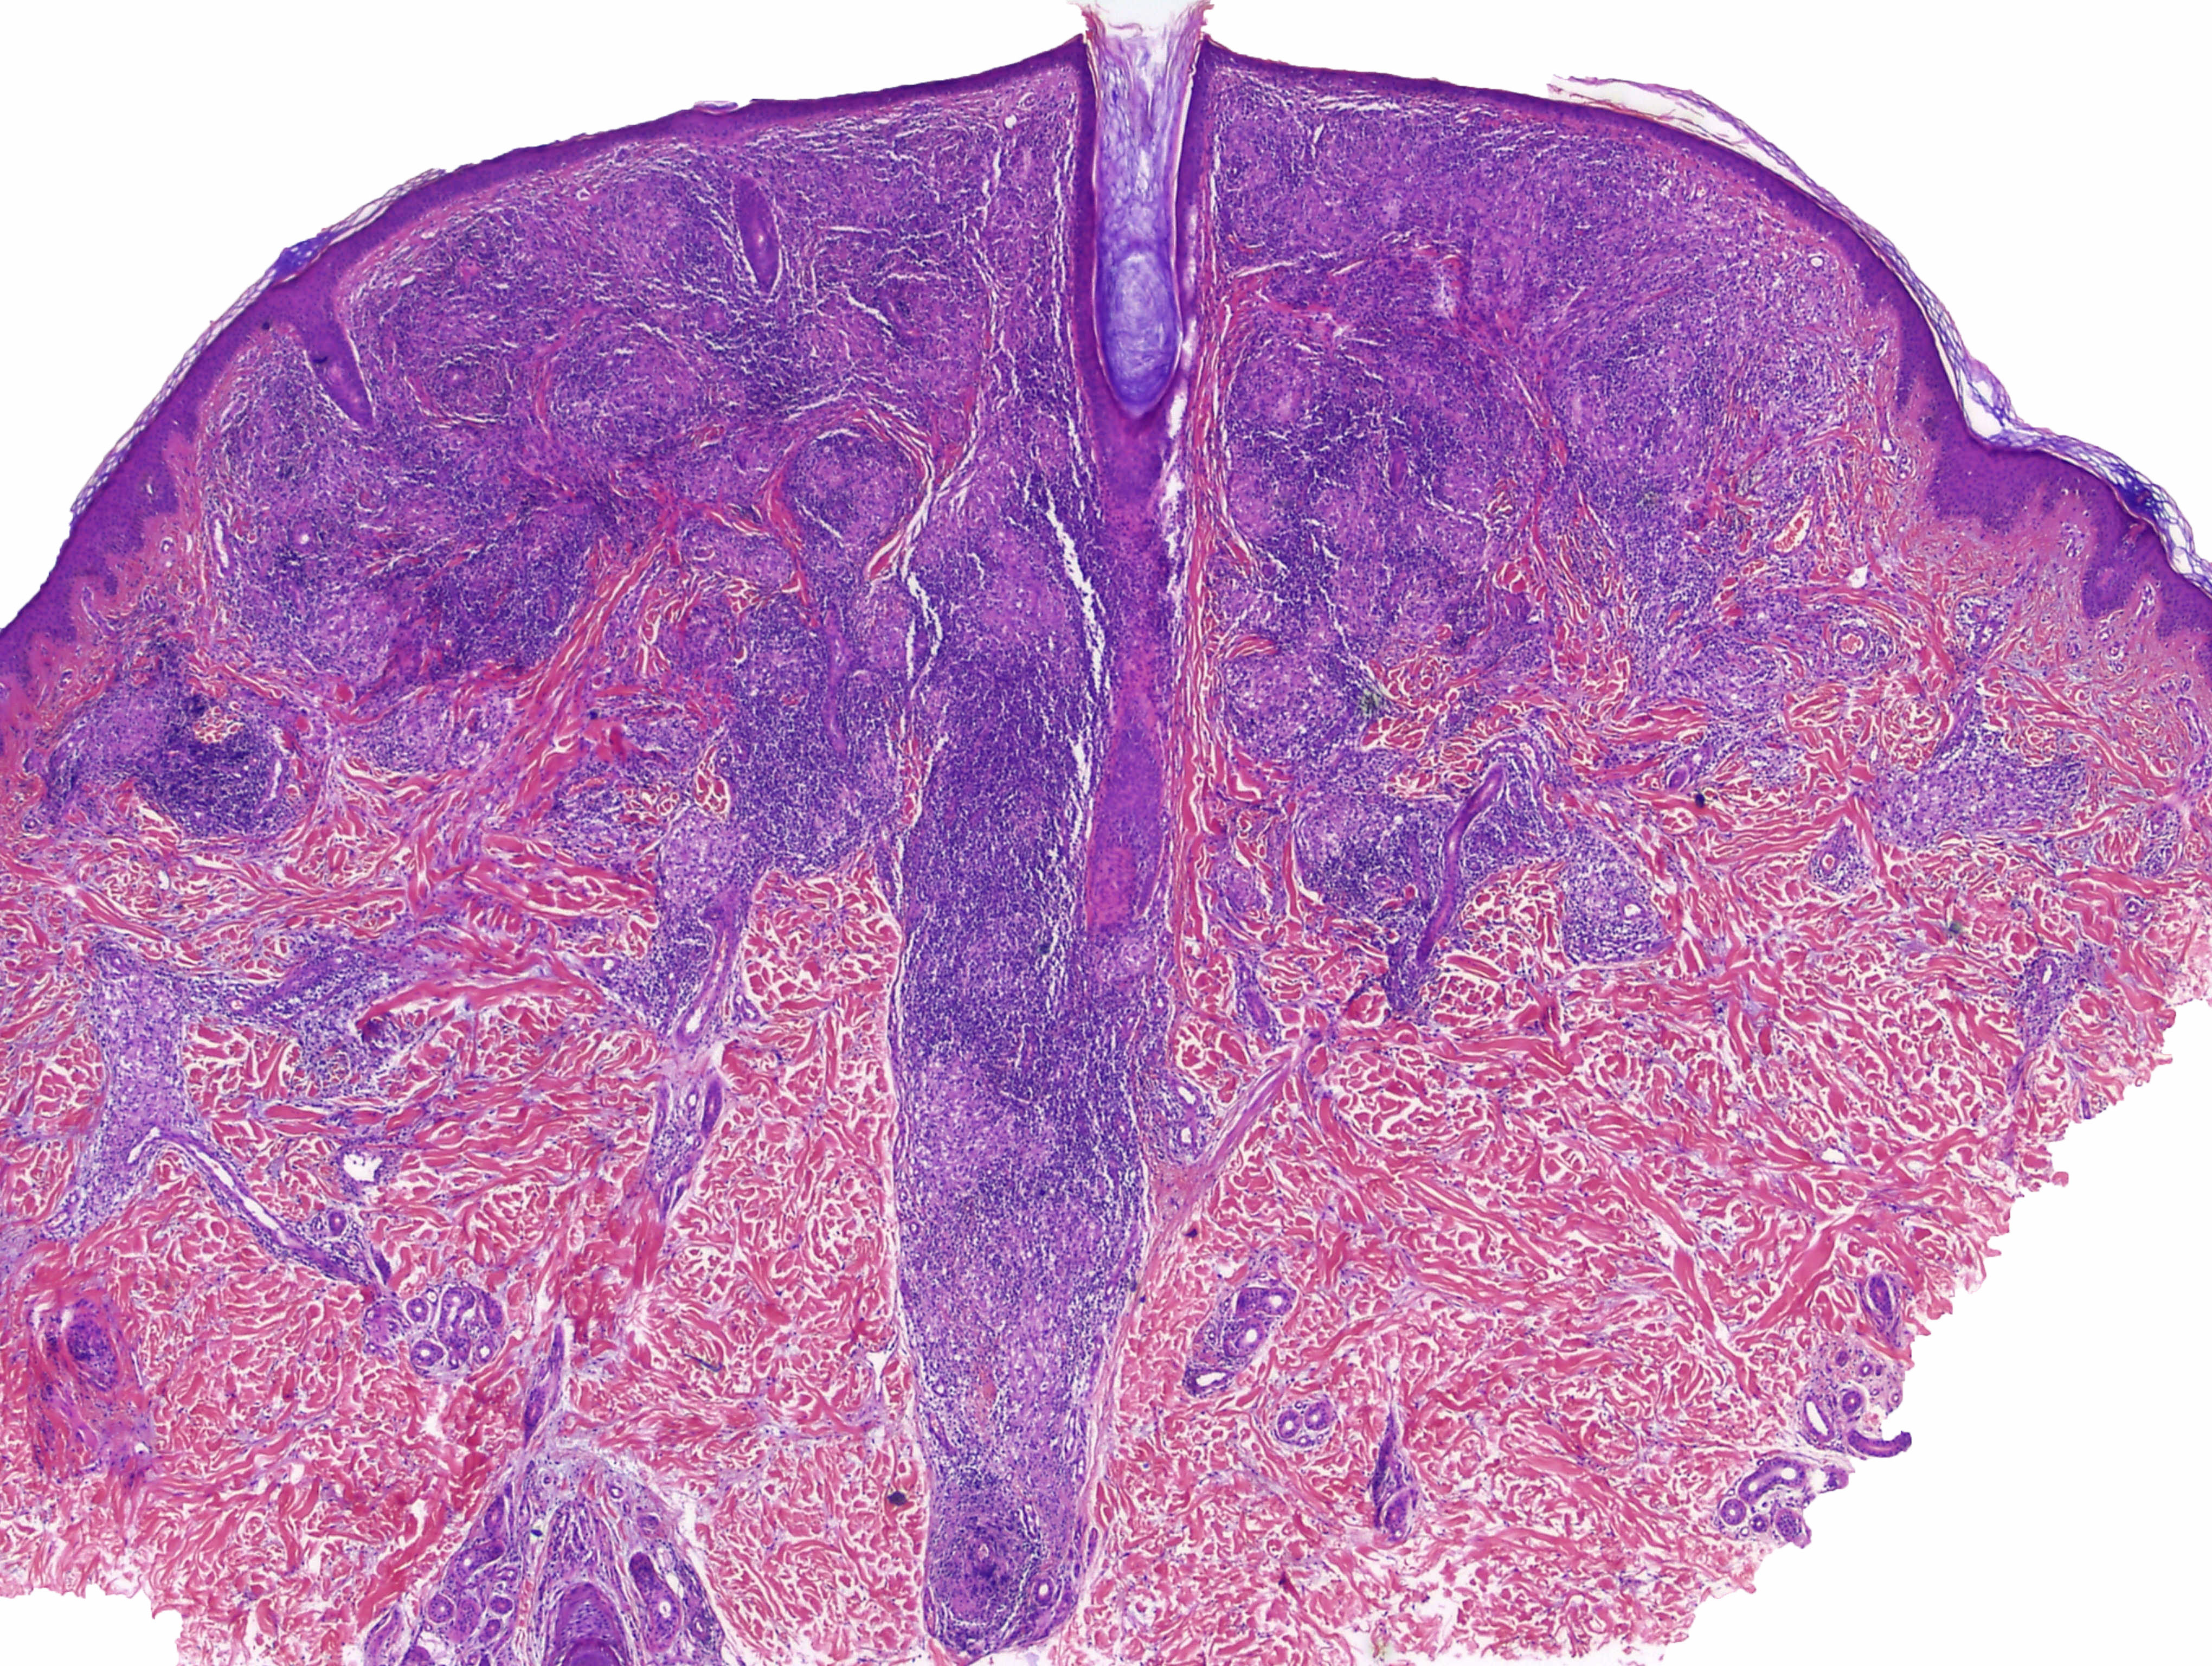

Cas dermatopaotologia. Dona de 36 anys amb pàpules pruriginoses vulvars

Juny 2013